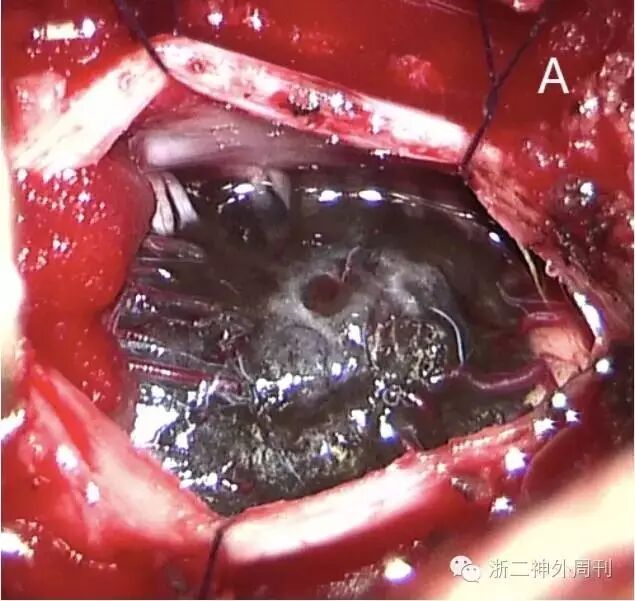

图1. 颈椎增强MRI,见C1-2偏左侧髓内占位,呈嵌入式生长,向后凸出髓外。A、B. 平扫,病灶T1呈不均质高信号,T2呈低信号;C、D. 增强后强化明显。